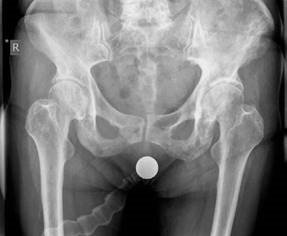

Structured Oral Hip Examination Question 3 EXAMINER : This is an anteroposterior (AP) radiograph of a 78-year…